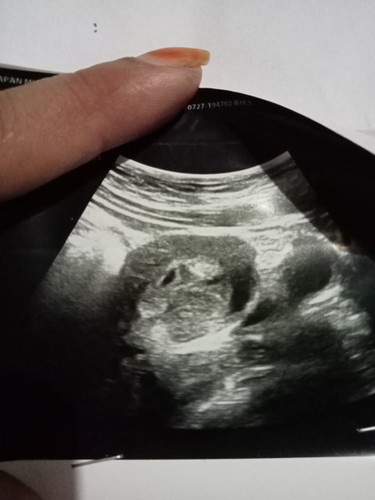

Hamil 5minggu

Bun mau tanya apa ini sudah masuk kantung 😌